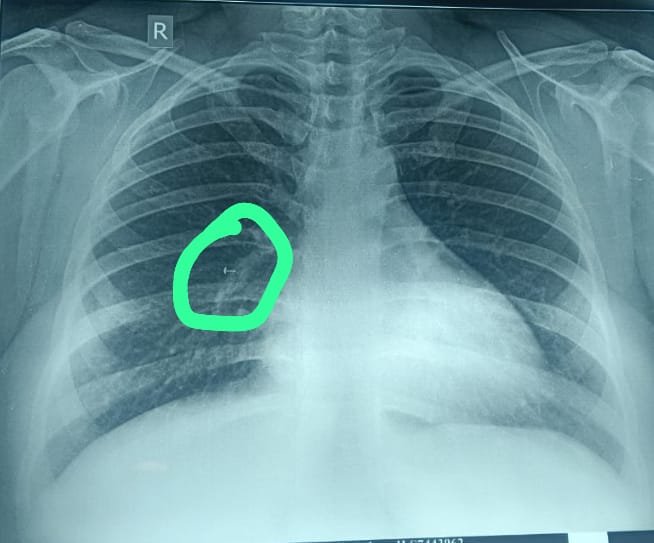

बरखा देवी, जो लगभग तीस साल की गृहिणी हैं (गोपनीयता के लिए नाम बदल दिया गया है) ने कुछ महीने पहले गलती से अपनी नाक की पिन में पेंच फंसा लिया था। घटना, जिसे शुरू में खारिज कर दिया गया था, ने एक नाटकीय मोड़ ले लिया जब कई महीनों बाद नाक की चोट के बाद एक एक्स-रे से उसके फेफड़े के अंदर फंसी वस्तु की उपस्थिति का पता चला।

स्थिति की जटिलता तब और बढ़ गई जब पहले उसका इलाज कर रहे डॉक्टर द्वारा पारंपरिक ब्रोंकोस्कोपी का उपयोग करके वस्तु को निकालने का प्रयास विफल हो गया और फिर उसे मेडिका सुपरस्पेशलिटी अस्पताल, कोलकाता के श्वसन चिकित्सा विभाग के निदेशक डॉ देबराज जश के पास भेजा गया।

डॉ. देबराज जश ने मामले के बारे में बताते हुए कहा, ”नोज पिन का स्क्रू बहुत ही असामान्य स्थिति में फंसा हुआ था। नुकीली वस्तु को उसके अनिश्चित स्थान, चोट लगने की संभावना और लंबे समय तक वहां मौजूद रहने के कारण होने वाली शारीरिक विकृति के कारण नियमित लचीले ब्रोन्कोस्कोप से बाहर लाना बेहद मुश्किल था।